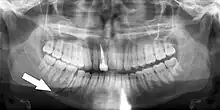

Injuries to supporting bone

This injury involves the alveolar bone and may extend beyond the alveolus.[5][6] There are five different types of alveolar fractures:

Trauma injuries involving the alveolus can be complicated as it does not happen in isolation, very often presents along with other types of tooth tissue injuries.

Signs of dentoalveolar fracture:

Investigation: Require more than one radiographic view to identify the fracture line.

Treatment: Reposition displaced teeth under local anaesthetic and stabilise the mobile segment with a splint for 4 weeks, suture any soft tissue lacerations.